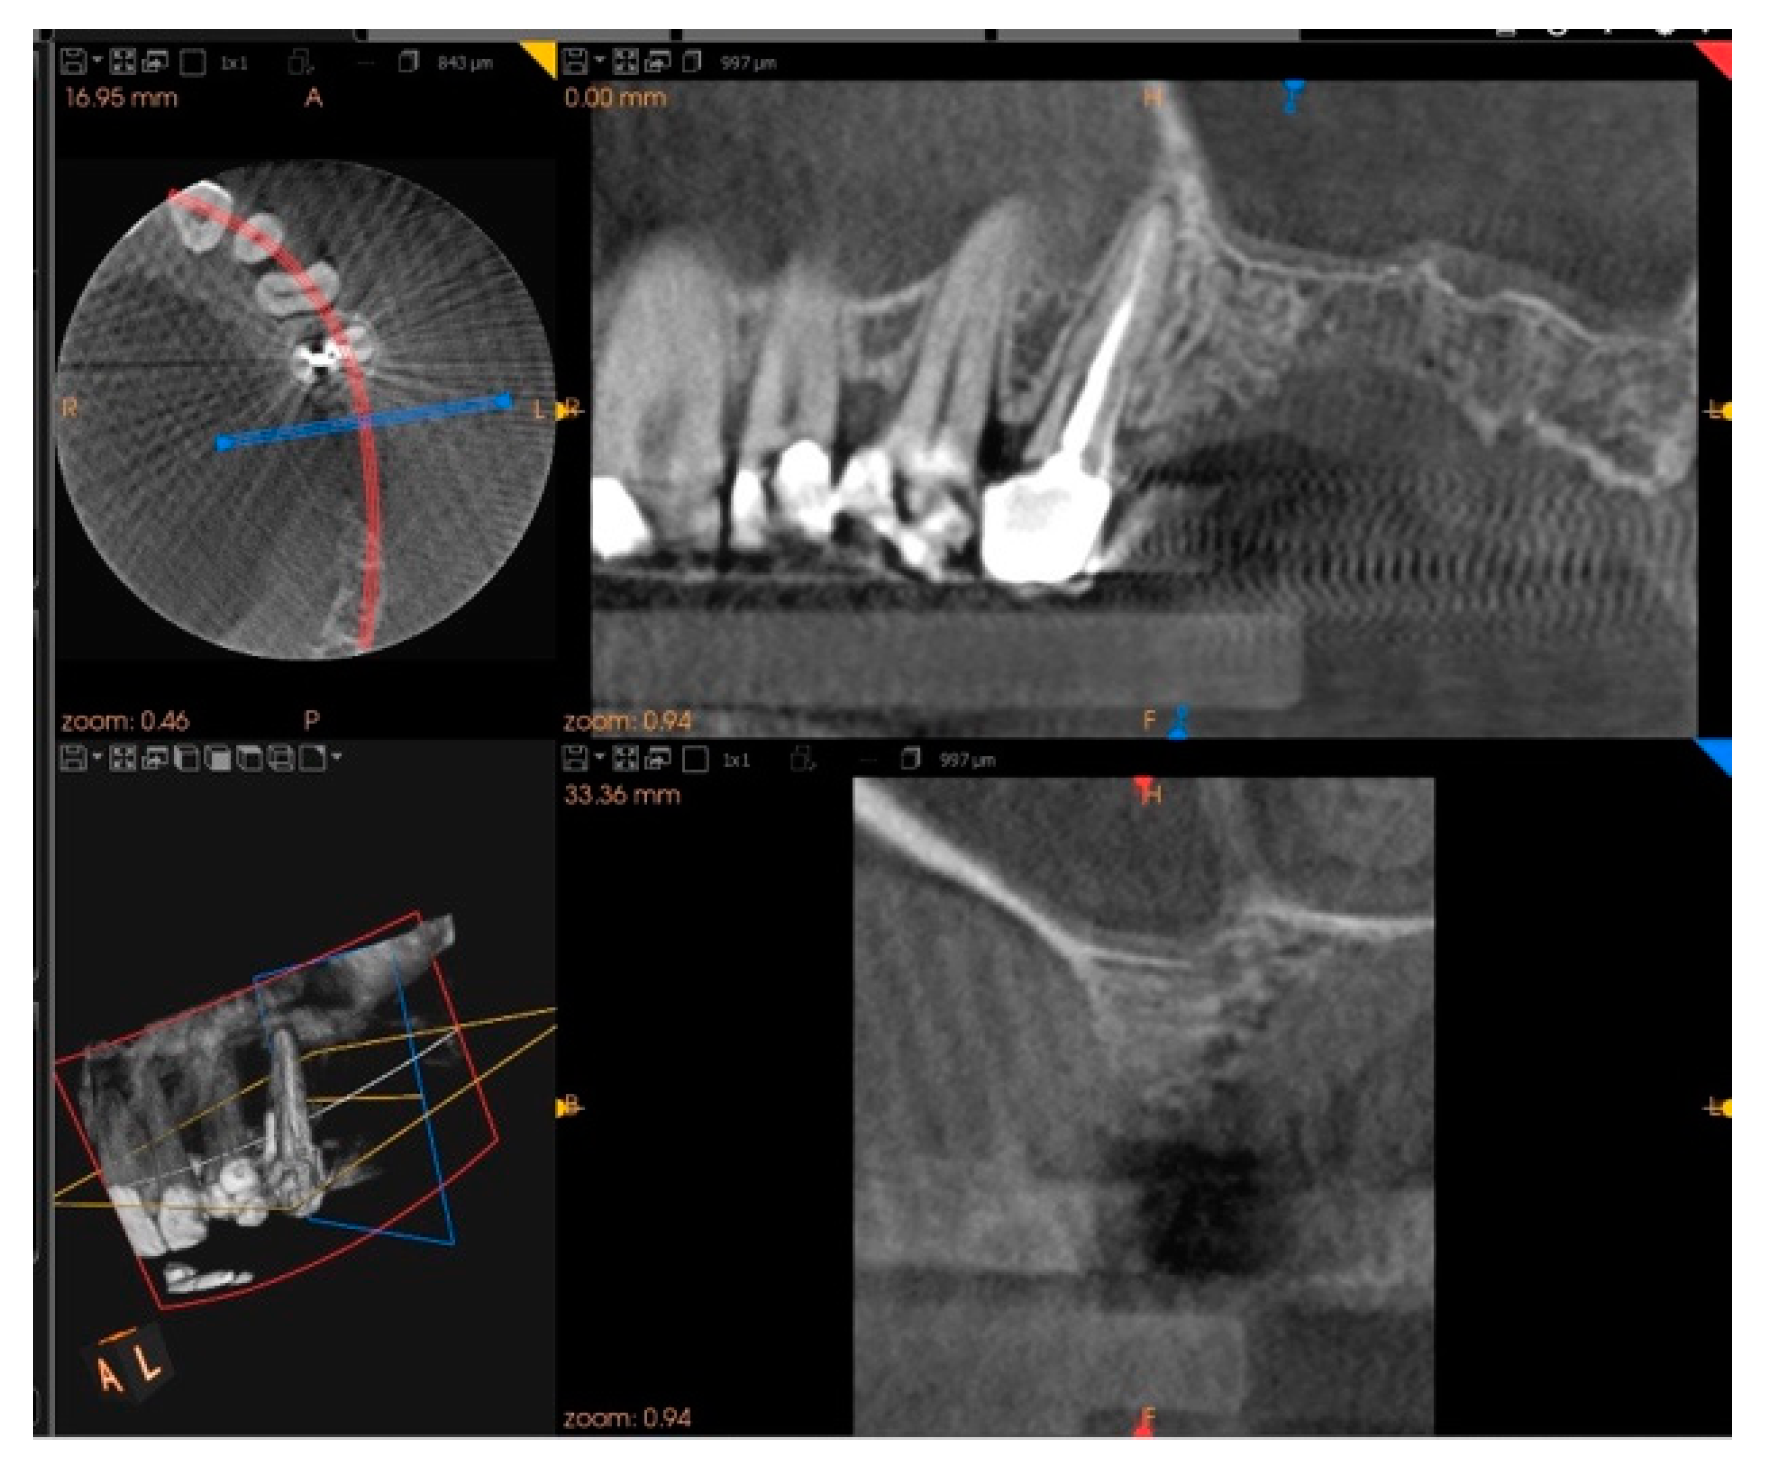

2. Case Report